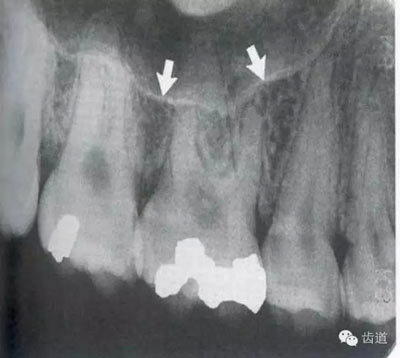

由升支前緣下部斜向前下方,為一密度高的帶狀影像。常重疊在第二、三磨牙牙冠處、頸部或根部,使牙髓室或根管不能清晰顯示